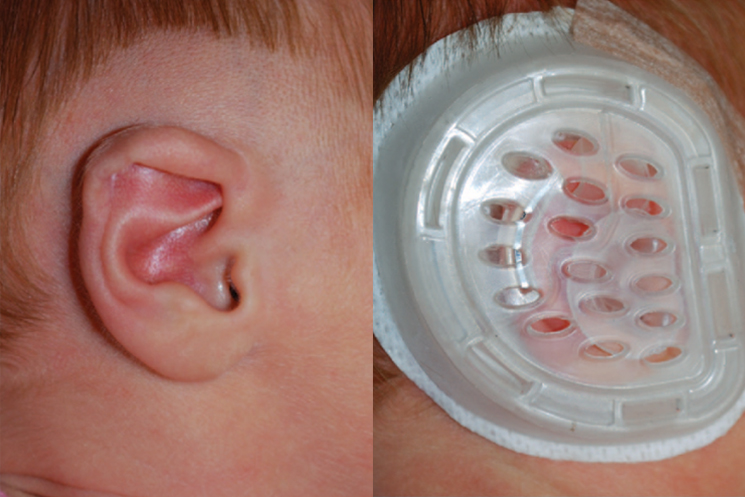

Specialized Braces:

We offer a range of specialized braces that are designed to be comfortable and effective. Our team of Orthodontists in Dubai will explain the different types of available braces and recommend the most suitable option for your child.